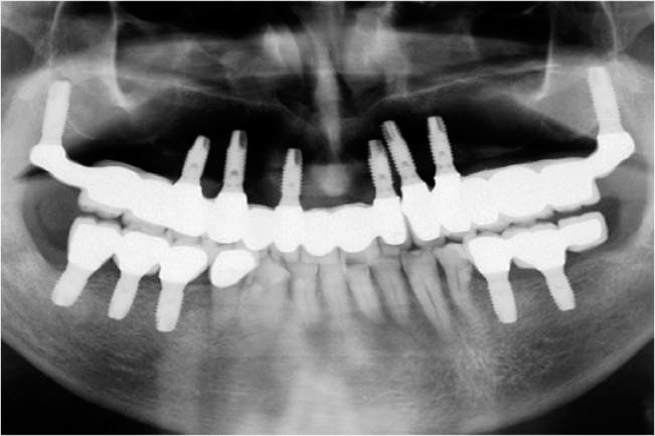

Pterygoid implants are inserted via simple surgery under local anaesthetic. The main difference between this technique and the technique employed for conventional implants is that long implants are used (with a minimum length of 16-20 millimetres) in order to penetrate up to the pterygoid processes. The implant is tilted towards the back of the mouth to reach the process region where it is possible to find sufficient bone to fix an implant, even in cases with a bone shortage in other areas. Osteotomes (similar to nail punches) are frequently used alongside drills commonly used in implantology, given that they allow for greater control and the little bone available may be condensed in an area instead of removing it when working the hole for the implant.

Pterygoid implants are recommended for edentulous patients missing back teeth as implants may be inserted in the premolar area, but not the molar area. As such, the patient can receive fixed teeth with a bridge between the normal premolar implants and the pterygoid implant.